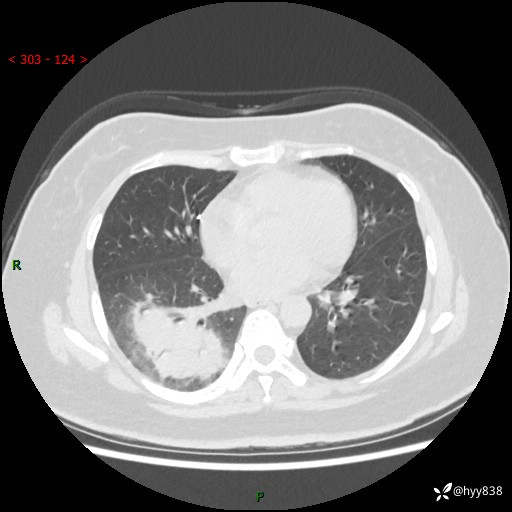

大叶性肺炎的表现形式,晒晒鉴别诊断吧…结果公布~

简要病史:患者8天前无明显诱因出现咳嗽、咳痰,为绿色脓痰,无明显加重与缓解因素,无高热、寒战,无呼吸困难,无大量脓痰,无哮鸣音,于当地医院行胸片示右下肺团块影,性质待定,予口服药物治疗症状未见明显改善,具体药名不详,为求进一步诊治来我院就诊,门诊以“肺占位性病变”收入我科进一步诊治。 患者自发病以来,精神、饮食尚可,睡眠欠佳,大小便正常,体力、体重未见明显异常。

辅助检查:CT

胸部CT平扫